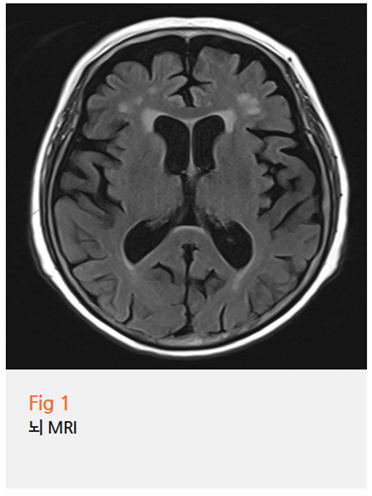

뇌 MRI와 GDS 검사였습니다.

뇌 MRI에는 연령에 비해 약간 위축 소견이 나왔어요.

이 정도로 치매를 확정하기는 힘들지만,

유의미한 결과물이기는 하죠.